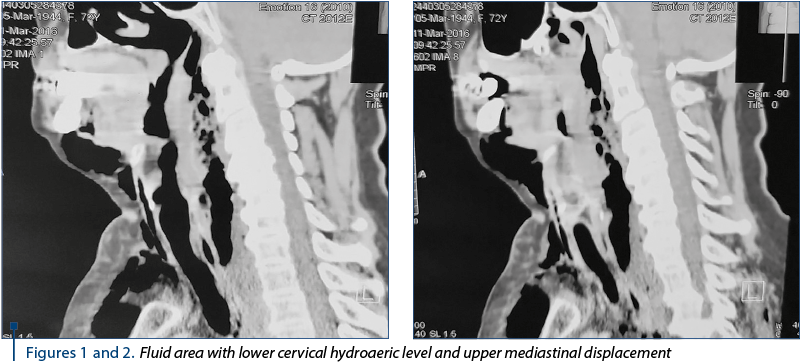

Figures 1 and 2. Fluid area with lower cervical hydroaeric level and upper mediastinal displacement

The urgent CT scan (2773/11.03.2016) revealed the diffuse thickening of the upper cervical and thoracic eso­phagus wall, with the delimitation of a fluid, inhomogeneous, diffusely delimited area with hydroaeric (Figures 1 and 2), cervical inferior and superior mediastinal visual (C5-T4) displayed posterolateral as it compressed the eso­phagus and partly the posterior wall of the trachea. Diffuse perilaryngeal infiltration with diminishing the laryngeal lumen, the infracentimetric hyper density zone of the suspected cervical inferior body (C7) anterolateral left in relation to esophageal wall; subcutaneous emphysema is marked on the cervical, thoracic and middles and posterior mediastinal level in the upper third (Figures 3 and 4). Bilateral pleural fluid. No changes in pulmonary transparency.